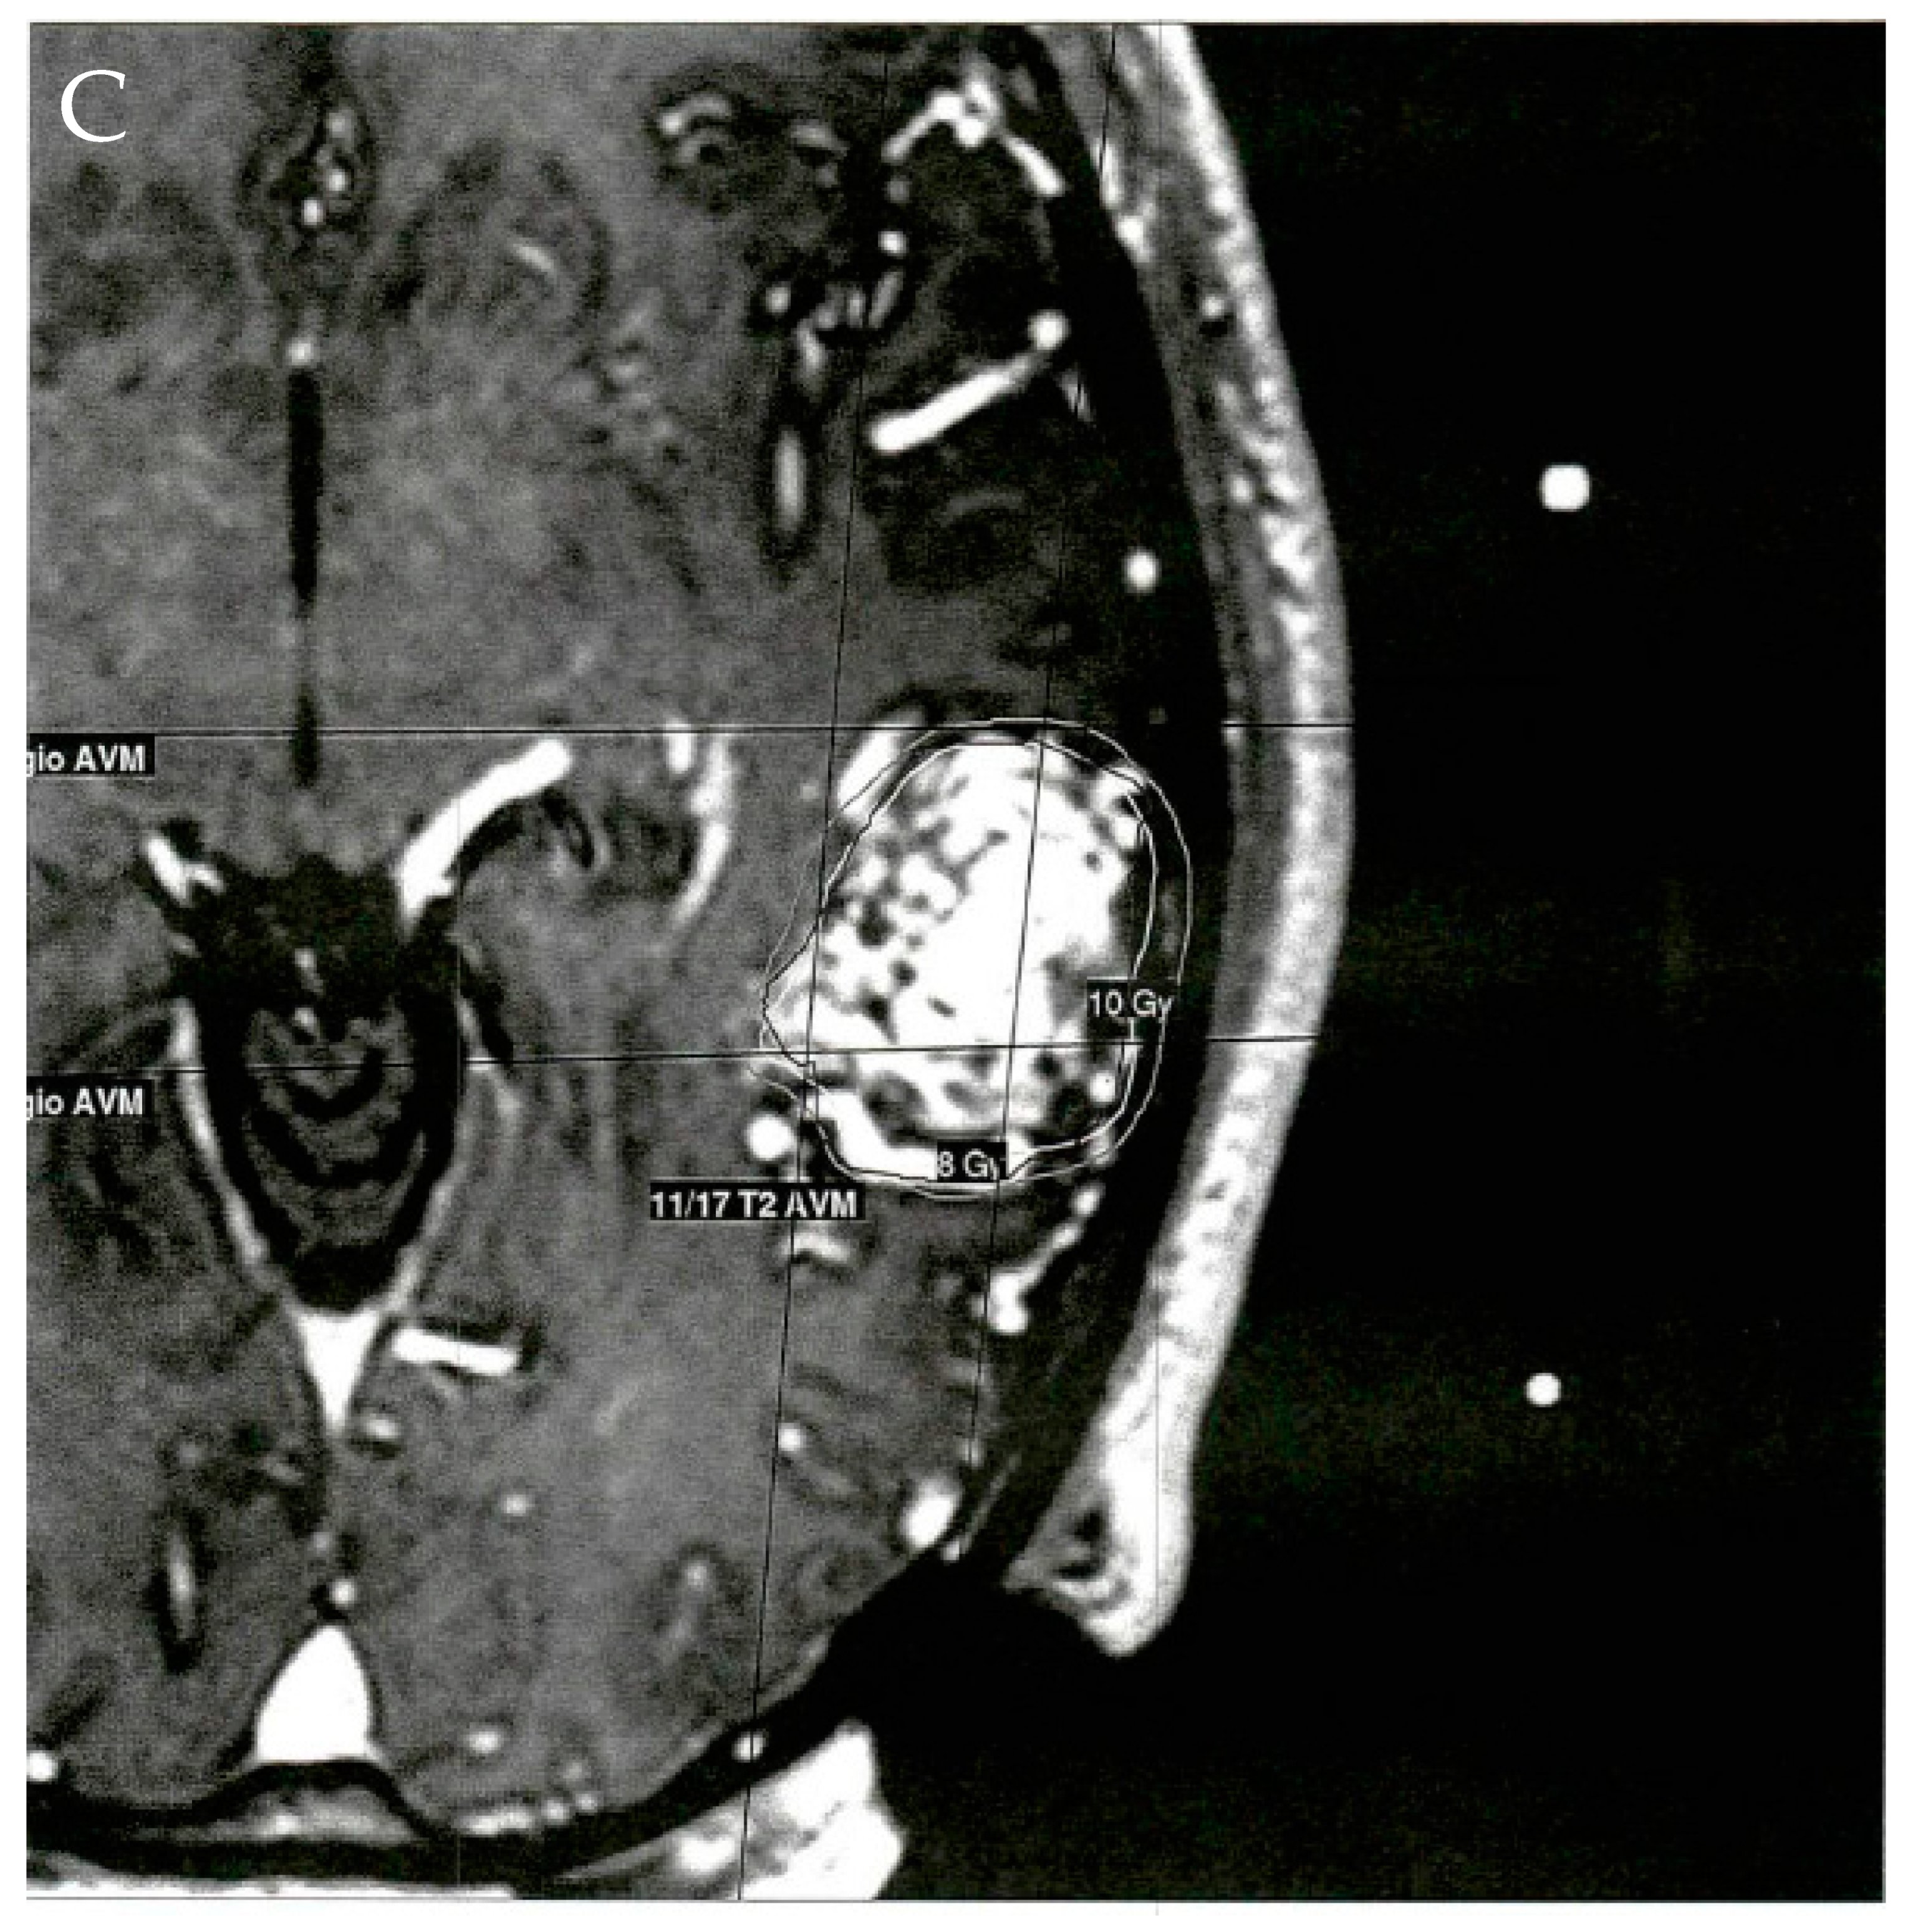

4.3. Stereotactic Radiosurgery

- El-Shehaby, A.M.; Reda, W.A.; Karim, K.M.A.; Eldin, R.M.E.; Nabeel, A.; Tawadros, S.R. Volume-Staged Gamma Knife Radiosurgery for Large Brain Arteriovenous Malformation. World Neurosurg. 2019, 132, e604–e612. [Google Scholar] [CrossRef] [PubMed]